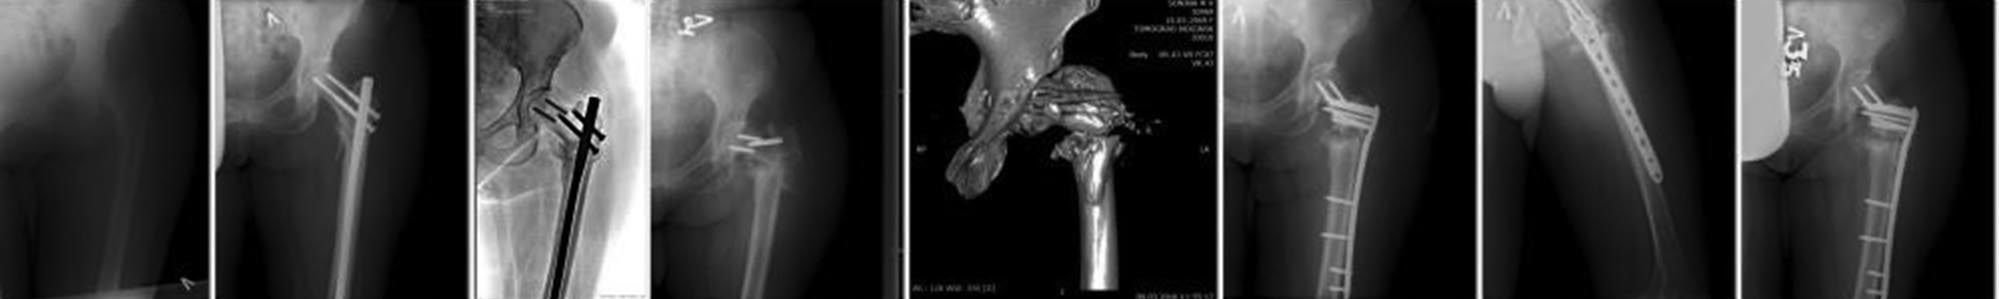

выкладываю случай. снимки в хронологическом порядке.

перелом-остеосинтез-миграция и перелом шеечных винтов(через 8 месяцев

после МОС) в то время больная ходит с тростью и испытывает периодические

боли в области верхушки вертела. мной расценено как консолидация и

принято решение удалить металл, а сращения то и нет((((смотрим КТ и РГ)

А.Н. Челноков рекомендовал перештифтовать с вальгизирующей остеотомией.

но я не стал... отправил в вышестоящую инстанцию и там сделали это..

остеотомия с костной пластикой и фиксация пластиной. после последней

операции прошло 6 месяцев, как видим сращения снова нет, и на последнем

снимке( Вам его не покажу, так как нет у меня) перелом пластины в

области перелома кости. вот так.